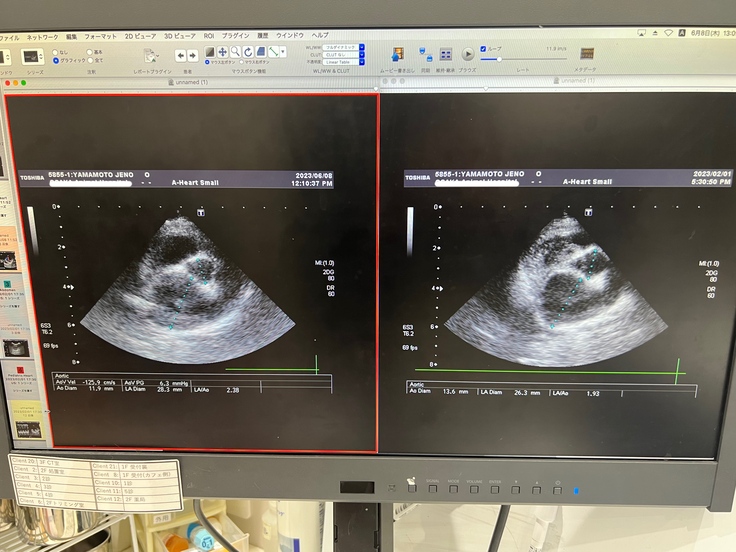

※心臓のエコー写真